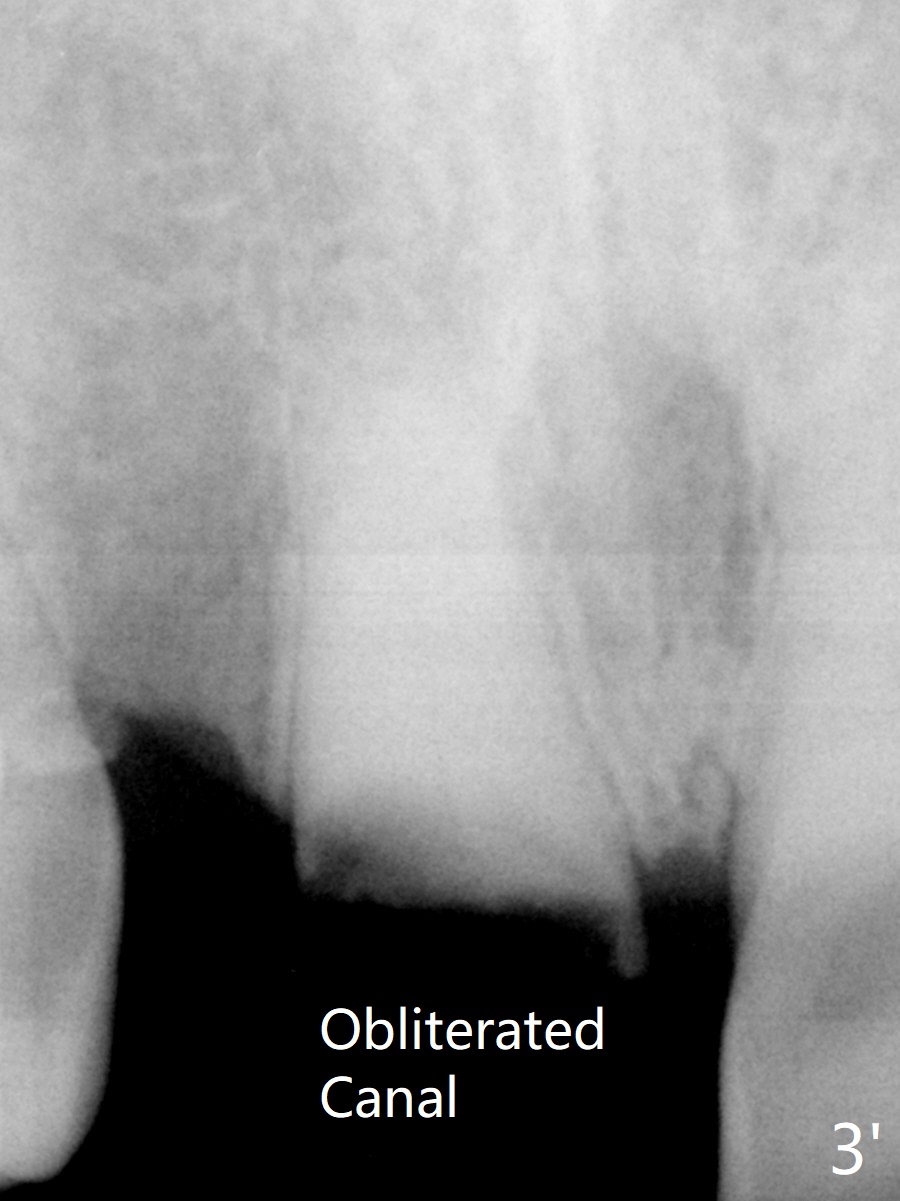

A 88-year-old man (CA) has severe xerostomia-induced caries. After caries control, implants will be placed at #7, 8 and 10 with narrow mesiodistal width (Fig.1,2). Note concavity at the apical buccal plate (*). To prevent perforation, an angled 1-piece implant will be used at #7. Try to place the implant in the middle of the alveolus (digital palpation while drilling) and let the angled abutment take care of the trajectory. To preserve papillae, flapless approach is going to be adopted. Initial depth at these sites will be 12,14 and 14 mm, respectively (Fig.3,4). Use Boley gauge to measure widths of the root to determine the diameter of the implant.